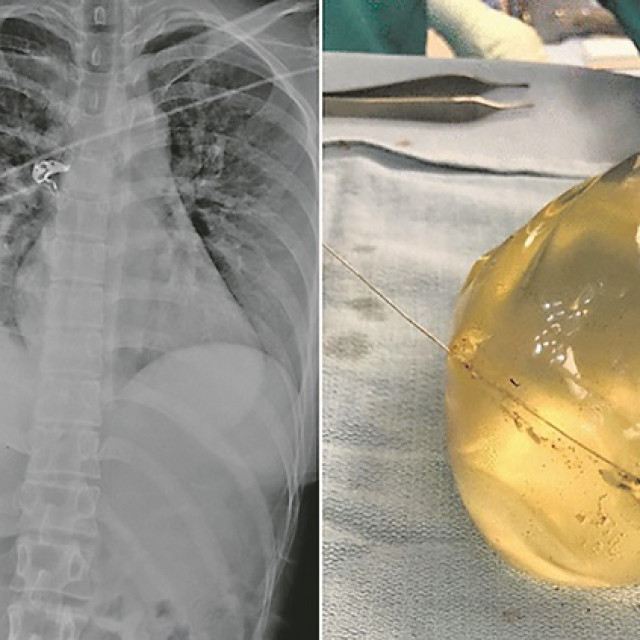

Na rendgenskoj snimci uspjeli su uočiti metak u desnoj bočnoj torakalnoj stijenci, kao i slomljeno rebro i mjehuriće zraka u lijevoj dojci te su zaključili da je metak “putovao” od lijeve dojke do desne torakalne stijenke.

Jednostavnije rečeno, metak je ušao kroz kožu na lijevoj strani prsa i zatim preusmjerio kretanje preko prsne kosti u desnu dojku i slomio rebro na desnoj strani. Metak je oštetio i desni implantat, koji su kirurzi, jednom kad su otvorili pacijenticu, pronašli u potpuno okrenutom položaju.

Žena je zadobila prostrijelnu ranu, slomljena rebra i oštećene implantate, ali je sve u svemu bila u puno boljem stanju nego što su očekivali. Implantati su joj izvađeni i prepisani su joj antibiotici. Policija je kasnije utvrdila da je metak, izvađen iz ženinih grudi, bio kalibra 0.40 obložen bakrenom ovojnicom.